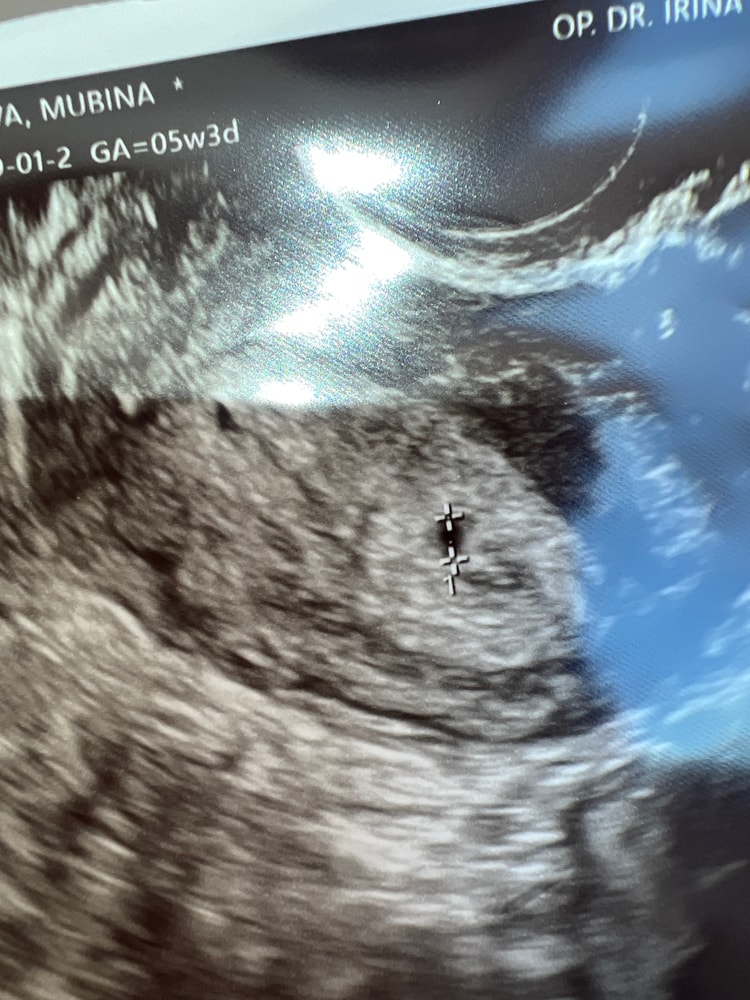

23 дпп узи